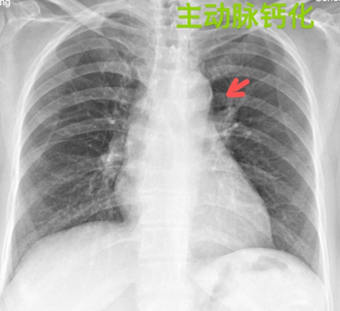

(5)主动脉钙化:是指钙质在主动脉管壁上沉积,导致主动脉管壁僵硬,弹性减弱。是动脉粥样硬化的一种表现。中老年人常见。